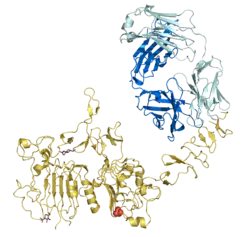

Receptor tyrosine-protein kinase erbB-2 is a protein that normally resides in the membranes of cells and is encoded by the ERBB2 gene. ERBB is abbreviated from erythroblastic oncogene B, a gene originally isolated from the avian genome. The human protein is also frequently referred to as HER2 (human epidermal growth factor receptor 2) or CD340 (cluster of differentiation 340).[5][6][7]

The ErbB family consists of four individual plasma membrane-bound receptor tyrosine kinases. One of which is erbB-2, and the other members being erbB-1, erbB-3 (neuregulin-binding; lacks kinase domain), and erbB-4. All four contain an extracellular ligand binding domain, a transmembrane domain, and an intracellular domain that can interact with a multitude of signaling molecules and exhibit both ligand-dependent and ligand-independent activity. Notably, no ligands for HER2 have yet been identified.[13][14] HER2 can heterodimerise with any of the other three receptors and is considered to be the preferred dimerisation partner of the other ErbB receptors.[15]